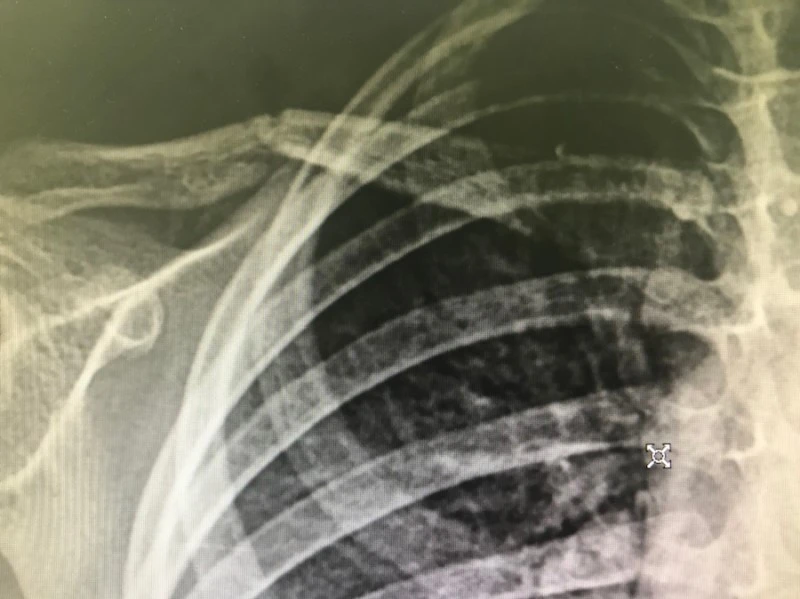

세 살 공주님이 응급실에 왔습니다. 겁먹은 눈망울 아래 오른쪽 볼에 울긋불긋 찰과상이 생겼네요. 목욕탕에서 넘어졌답니다. 오른 어깨가 아프다길래 사진을 찍었습니다. 가벼운 타박상이길 기대했는데 아이쿠, 이런! 우측 쇄골이 부러졌네요. 히라가나와 가타카나의 へ(he)자처럼.